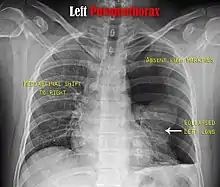

Chest X-ray

A plain chest radiograph, ideally with the X-ray beams being projected from the back (posteroanterior, or "PA"), and during maximal inspiration (holding one's breath), is the most appropriate first investigation.[25] It is not believed that routinely taking images during expiration would confer any benefit.[26] Still, they may be useful in the detection of a pneumothorax when clinical suspicion is high but yet an inspiratory radiograph appears normal.[27] Also, if the PA X-ray does not show a pneumothorax but there is a strong suspicion of one, lateral X-rays (with beams projecting from the side) may be performed, but this is not routine practice.[14][18]

It is not unusual for the mediastinum (the structure between the lungs that contains the heart, great blood vessels, and large airways) to be shifted away from the affected lung due to the pressure differences. This is not equivalent to a tension pneumothorax, which is determined mainly by the constellation of symptoms, hypoxia, and shock.[13]

The size of the pneumothorax (i.e. the volume of air in the pleural space) can be determined with a reasonable degree of accuracy by measuring the distance between the chest wall and the lung. This is relevant to treatment, as smaller pneumothoraces may be managed differently. An air rim of 2 cm means that the pneumothorax occupies about 50% of the hemithorax.[14] British professional guidelines have traditionally stated that the measurement should be performed at the level of the hilum (where blood vessels and airways enter the lung) with 2 cm as the cutoff,[14] while American guidelines state that the measurement should be done at the apex (top) of the lung with 3 cm differentiating between a "small" and a "large" pneumothorax.[28] The latter method may overestimate the size of a pneumothorax if it is located mainly at the apex, which is a common occurrence.[14] The various methods correlate poorly but are the best easily available ways of estimating pneumothorax size.[14][18] CT scanning (see below) can provide a more accurate determination of the size of the pneumothorax, but its routine use in this setting is not recommended.[28]

Not all pneumothoraces are uniform; some only form a pocket of air in a particular place in the chest.[14] Small amounts of fluid may be noted on the chest X-ray (hydropneumothorax); this may be blood (hemopneumothorax).[13] In some cases, the only significant abnormality may be the "deep sulcus sign", in which the normally small space between the chest wall and the diaphragm appears enlarged due to the abnormal presence of fluid.[15]